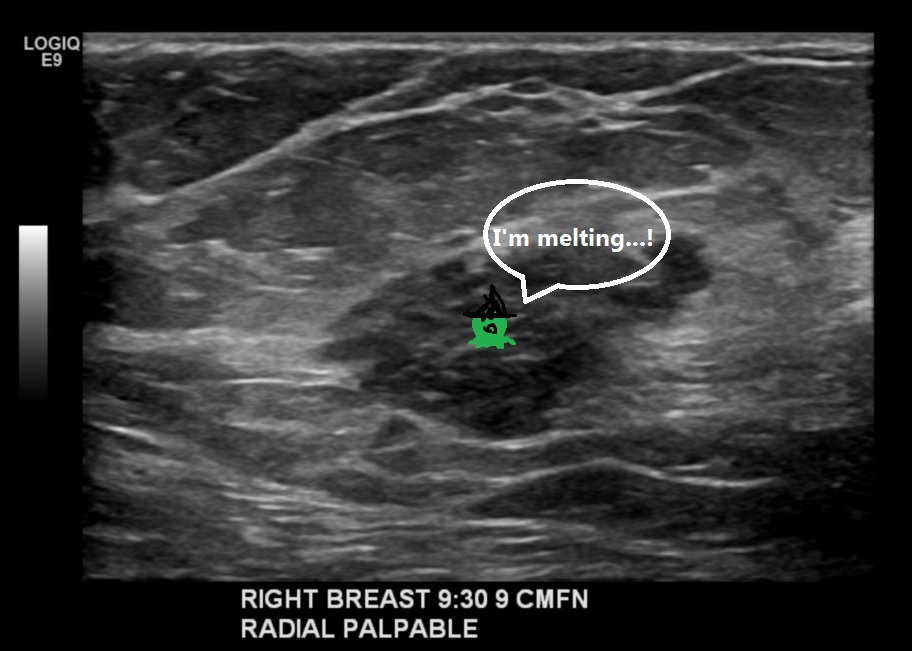

What the plan is, though, is to start with a lumpectomy. On examining the bad boob, Supe was unable to feel any sign of Turdy the tumor! He said he’s “thrilled” with the chemo. So all he’ll have to remove is the little metal clip that Dr. Moviestar put in when he did the original biopsy. He’ll take that plus some surrounding tissue. It will most likely be a small enough amount that while Right Boob will have a scar, it won’t be the ginormous shark bite disfigurement I was imagining.